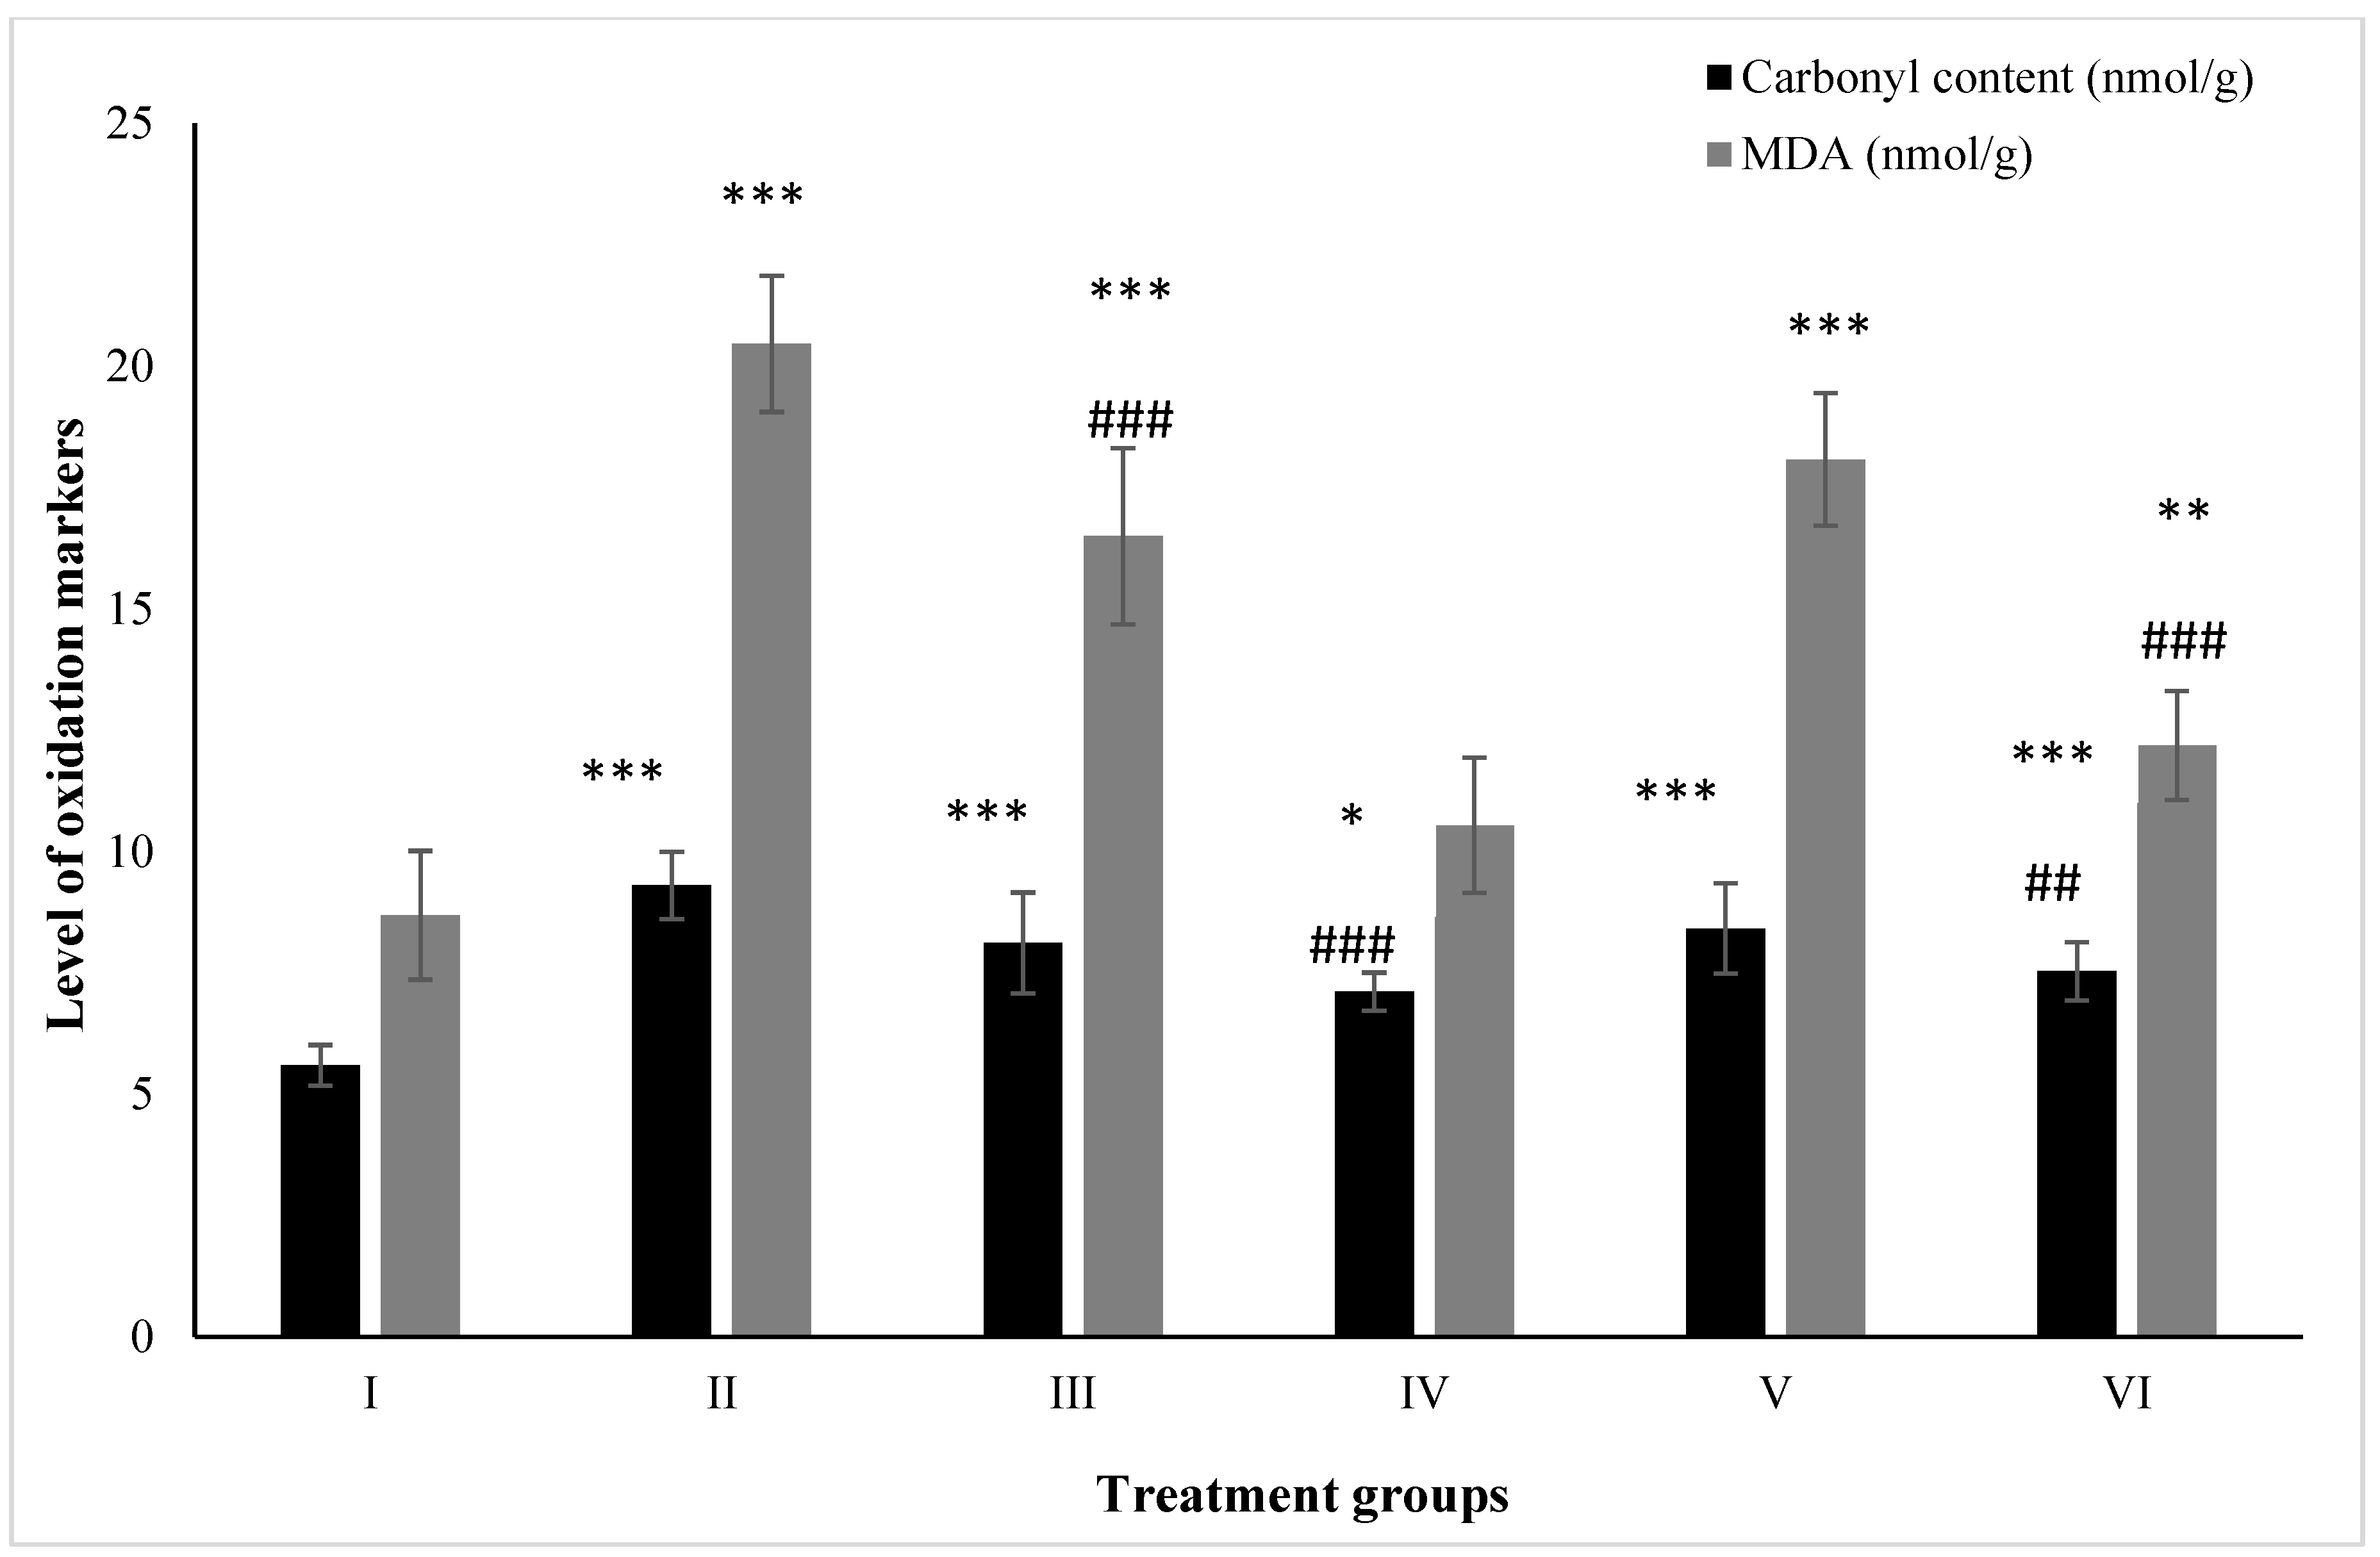

2.5. Effect on Macromolecular Oxidation

2.5.1. Carbonyl Content

2.5.2. MDA